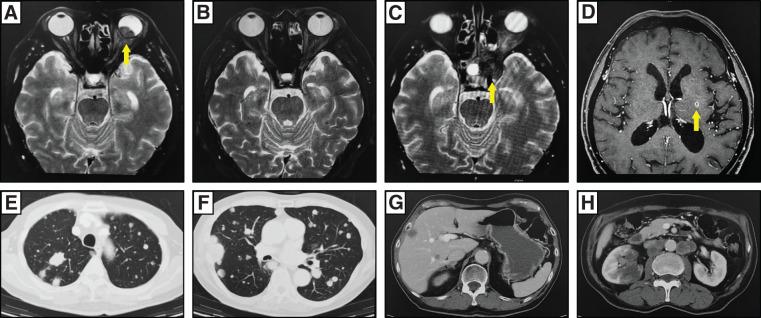

A 67-year-old man underwent curative surgery and adjuvant chemotherapy for ascending colon cancer. Two years later, pulmonary recurrence was detected and surgically resected. At 2 years and 5 months postoperatively, he developed visual impairment in the left eye, which led to the diagnosis of choroidal metastasis. A combination of systemic chemotherapy and local radiotherapy resulted in tumor shrinkage and relief of ocular pain. With additional local treatments administered in response to subsequent recurrences, the patient achieved long-term survival-5 years and 6 months after surgery and 3 years after the diagnosis of choroidal metastasis. A review of 22 reported cases of choroidal metastasis from colorectal cancer published since 2000 revealed that most patients had multi-organ metastases at the time of diagnosis. The average survival following the diagnosis of ocular metastasis was 10.4 months, indicating a poor prognosis. By contrast, local treatments-such as radiotherapy and intravitreal injections-contributed to symptom relief and the maintenance of quality of life. This case represents a valuable example of long-term survival achieved through combined local therapies.

一名67岁男性因升结肠癌接受了根治性手术及辅助化疗。两年后,发现肺部复发并进行了手术切除。术后2年零5个月,他左眼出现视力障碍,进而诊断为脉络膜转移。全身化疗与局部放疗相结合使肿瘤缩小,眼部疼痛缓解。针对后续复发进行了额外的局部治疗,患者实现了长期生存——术后5年零6个月,脉络膜转移诊断后3年。对2000年以来报道的22例结直肠癌脉络膜转移病例的回顾显示,大多数患者在诊断时已有多器官转移。眼部转移诊断后的平均生存期为10.4个月,预后较差。相比之下,局部治疗,如放疗和玻璃体内注射,有助于缓解症状并维持生活质量。本病例是通过联合局部治疗实现长期生存的一个有价值的例子。